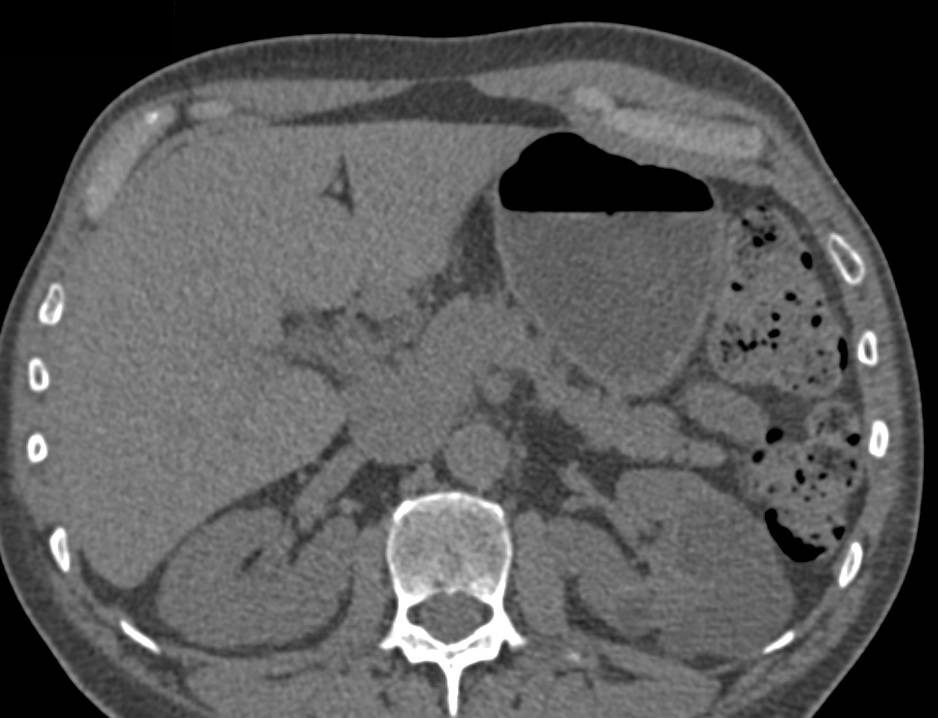

Recurrent Renal Cell Carcinoma Metastatic to the Pancreas